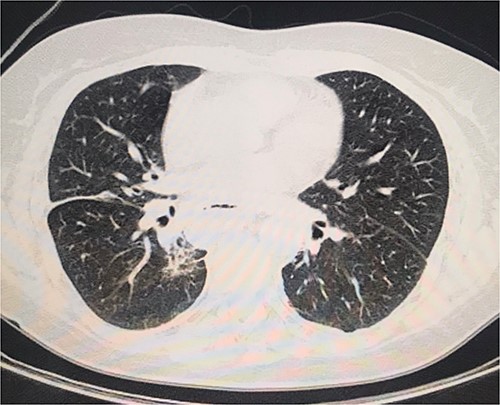

On the second day postoperatively, the patient presented with dyspnea and fatigue; a new chest CT evidenced a hydropneumothorax on the left (Fig. 3). Water-seal chest drainage was performed, with an adequate re-expansion despite the chronicity of the hernia and improvement in ventilatory parameters and symptoms (Fig. 4). She was discharged after 9 days of hospitalization. Currently, she is doing well with a satisfactory response to treatment.

Second day follow-up showed a hydropneumothorax on the left chest CT scan.